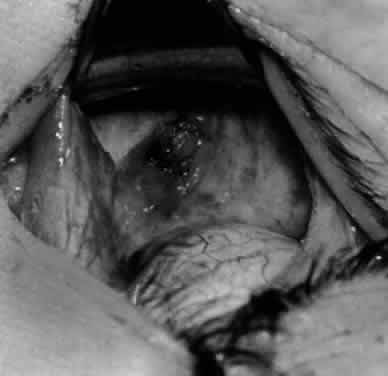

Fig. 28. The inferior oblique muscle is drawn further into the operative field, and a 3-0 Vicryl suture ligature is applied about the belly of the muscle.

Fig. 29. Cautery is used to sever the inferior oblique muscle and to provide hemostasis.

Fig. 30. The stump of muscle is placed through the Tenon's capsule opening. The surgeon must apply sufficient cautery to prevent postoperative bleeding.